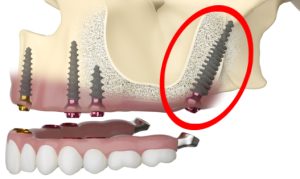

Pterygoid Dental Implants

Pterygoid Dental Implants are the go-to choice for patients in need of comprehensive oral restoration who lack sufficient bone density in the upper jaw to support traditional implants.

Pterygoid Dental Implants represent an advanced option for complete oral rehabilitation in individuals who face the challenge of deficient bone volume in the upper jaw. These innovative implants derive their name from their unique placement in the pterygoid plate—a component of the sphenoid bone situated at the rear of the upper jaw.

One of the challenges with the All On 4 dental implant prosthetics is the cantilever effect, where the prosthetic teeth extend beyond the last implant, creating a lever that can lead to stress and potential failure. Pterygoid implants offer a solution to this cantilever issue by providing additional anchorage in the pterygoid plate, allowing for extended support without the drawbacks of a cantilever.

Pterygoid Dental Implants

Pterygoid Dental Implants are the go-to choice for patients in need of comprehensive oral restoration who lack sufficient bone density in the upper jaw to support traditional implants.

Pterygoid Dental Implants represent an advanced option for complete oral rehabilitation in individuals who face the challenge of deficient bone volume in the upper jaw. These innovative implants derive their name from their unique placement in the pterygoid plate—a component of the sphenoid bone situated at the rear of the upper jaw.

One of the challenges with the All On 4 dental implant prosthetics is the cantilever effect, where the prosthetic teeth extend beyond the last implant, creating a lever that can lead to stress and potential failure. Pterygoid implants offer a solution to this cantilever issue by providing additional anchorage in the pterygoid plate, allowing for extended support without the drawbacks of a cantilever.